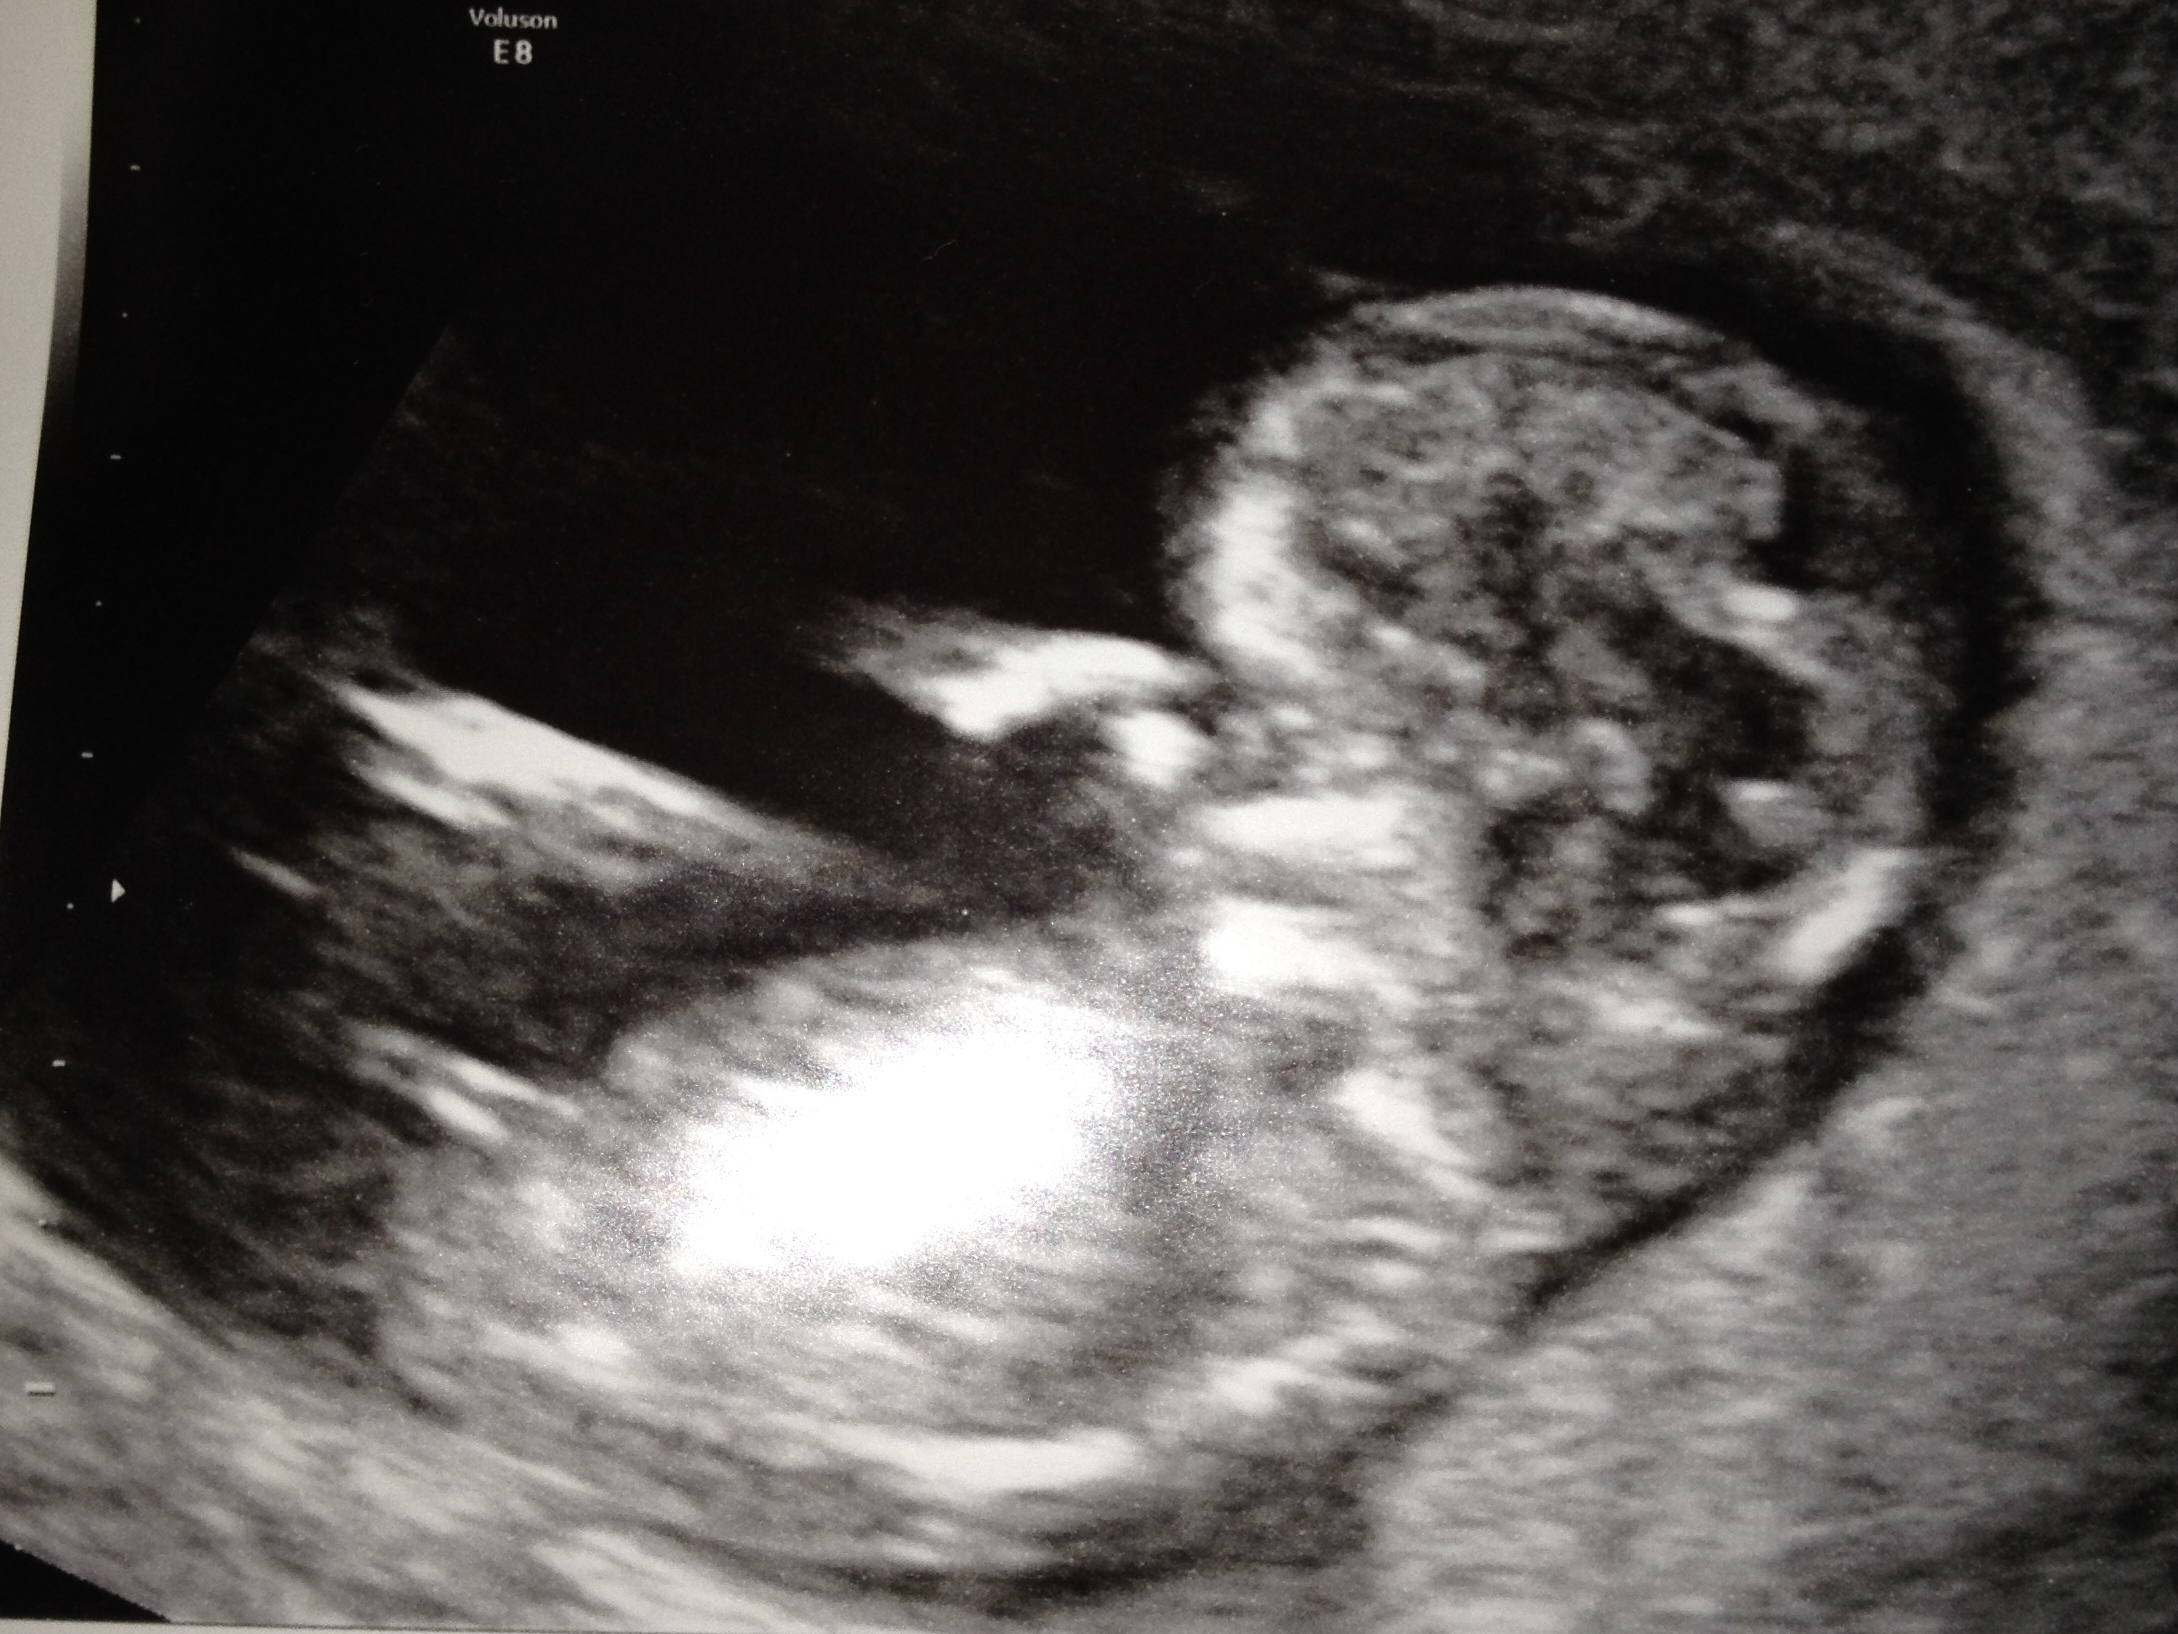

Had a scan at 12+5 with a really clear nub! My immediate guess was girl for the nub as its in line with the spine (feel free to correct me if I'm wrong!), I have no clue what to look for with skull theory!

Attachment 17735

leaning girl but that angle is hard with baby curved!

I agree the curve of baby's spine is not giving us a good idea of the angle of the nub- so a tentative girl lean bc it's long past the bum but would be more confident if spine was flat

I'm leaning boy too, there's a bit of an angle happening there.

I'm seeing a bit of angle too. But gestation would suggest that a boy would be much more angled at this stage. I'm not really confident either way. Sorry!

Hi I see you're scan pic on one of the other sites and guessed blue and then gave more of a pink lean with the second pic you put up, but i keep looking at yours as the more I look the more I feel pink! I think the first pic (second pic on here) baby is very curled so is more deceptive with the rise, so I'm changing my mind and going for pink! GL xx